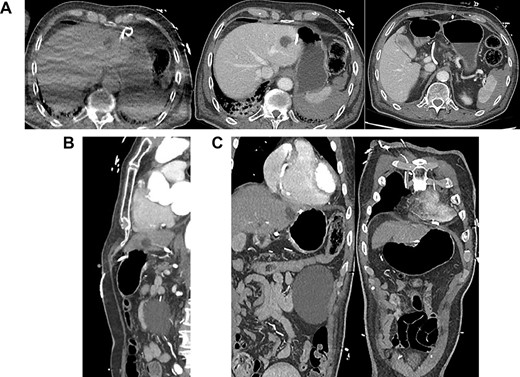

(A) Axial CT-angiogram: side drainage holes are apparent in the pericardium and the abdominal cavity; the drain courses anteriorly and abuts the medial aspect of the liver and stomach ~3 cm superiorly and medially to the course of the drain insertion forming a large loop; free gas is apparent at the right anterior liver; (B) sagittal CT-angiogram: subxiphoid approach with peritoneal entry; (C) coronal CT-angiogram: placement of catheter in pericardium; catheter traverses segment 2/3 liver.

The CT-angiogram showed no evidence of pericardial effusion, suggestive of successful treatment by drain placement (Fig. 1). It showed pneumo- and haemoperitoneum and that the drain appeared to course between the lesser curvature of the stomach and the liver with an intraperitoneal loop. There was no evidence of contrast leak to suggest active bleeding. A second CT of the abdomen with oral contrast provided no evidence of extravasation to suggest gastric perforation.